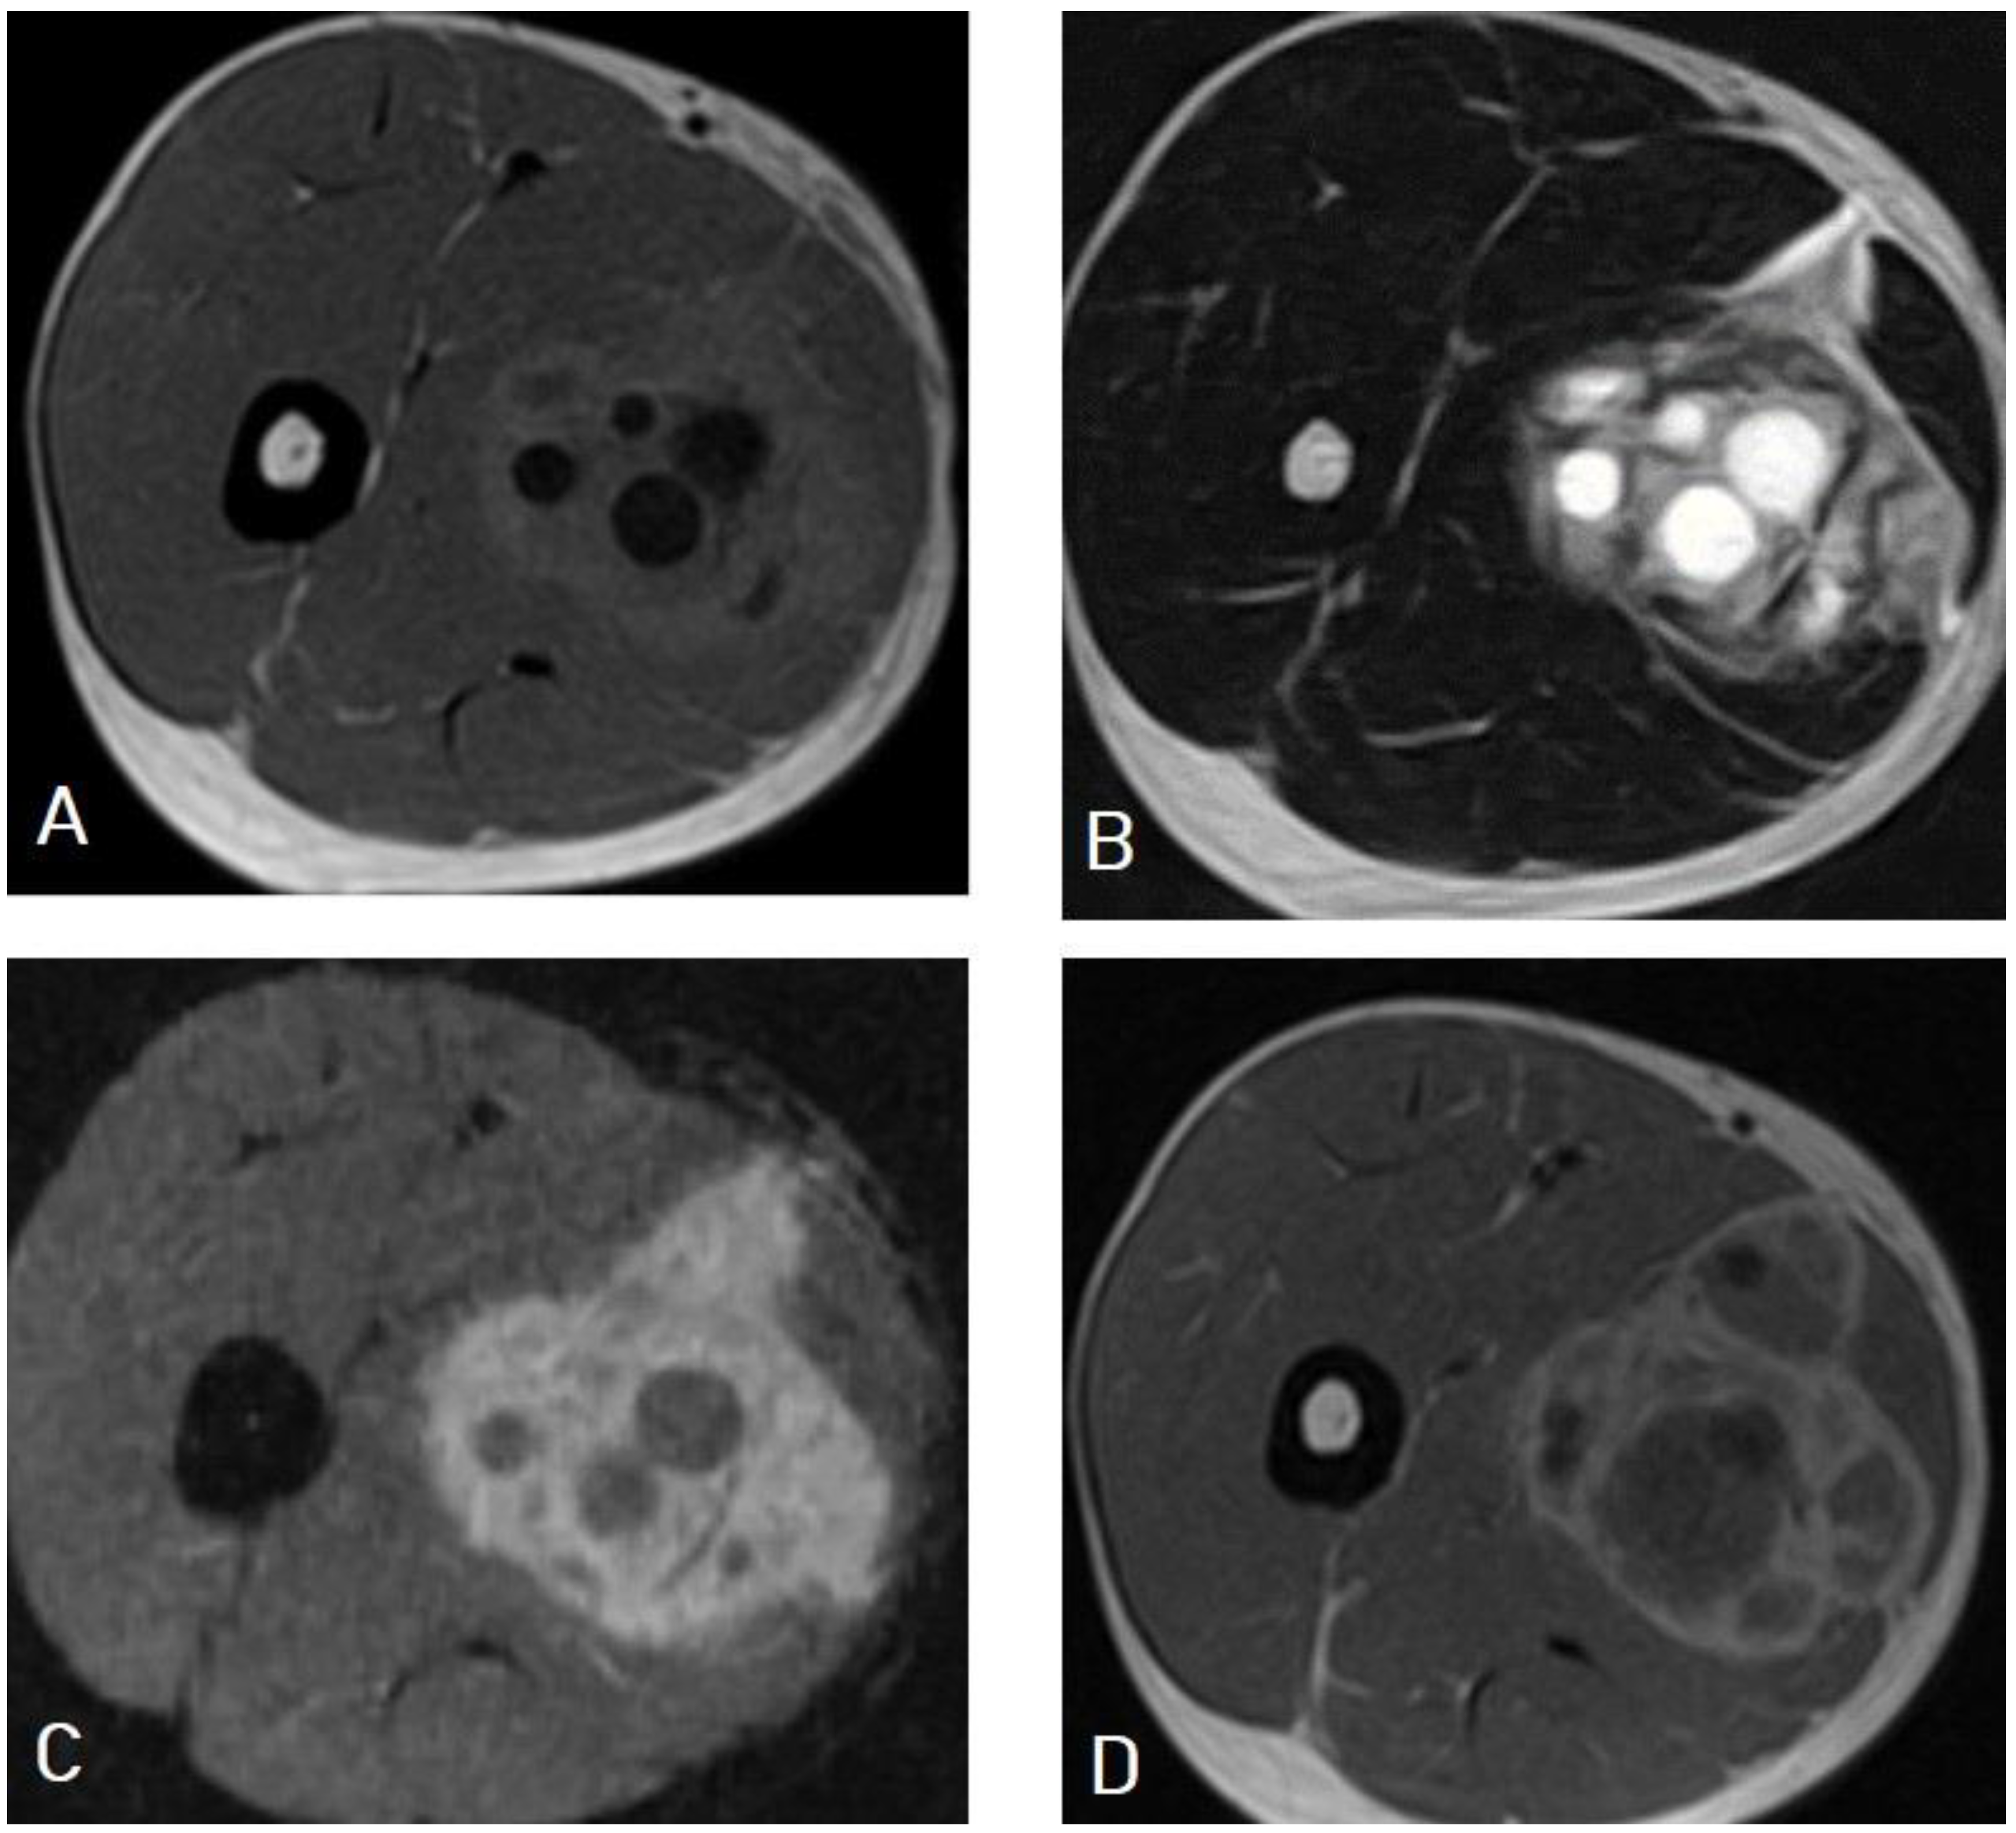

5.1. Hydatid Cysts of the Liver

| Erdem et al. [22] | Liver hydatid cyst can mimic multiple cystic or solid lesions of the liver, such as the following: 1: Simple liver cysts. 2: Choledochal cysts. 3: Caroli’s disease. 4: Hemangioendotheliomas. 5: Mesenchymal hamartomas. 6: Teratomas. |